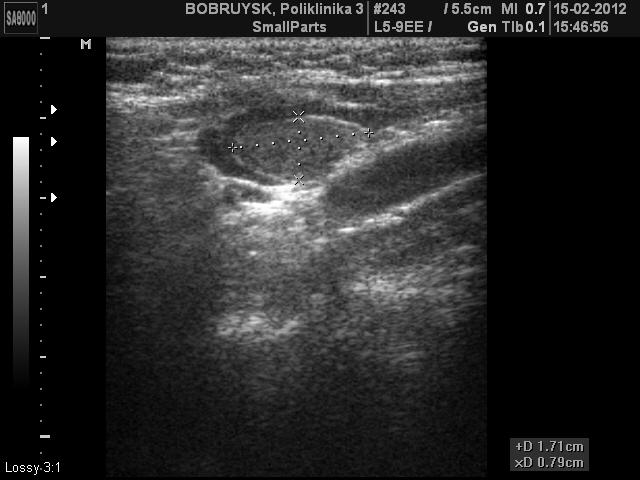

Вот такой ультразвуковой случай образования в проекции щитовидной железы.

Пациентка 66 лет. Жалоб не предъявляет

Стоит на учете у эндокринолога, диагноз не помнит, но говорит узел какой то года три назад, пунктировали, но результатов не знает и не помнит.

ADENOMA_5.JPG

ADENOMA_11.JPG

Первое впечатление - ХАИТ, псевдоузловая форма.

Я конечно же не "свадебщик", по этому в данном случае, рассматриваю вариант с аденомой паращитовидной железы. Хотя структура самой щитовидной железы, которая мной отражена не достаточно хорошо в ролике, действительно похожа на АИТ.

рассматриваю вариант с аденомой паращитовидной железы.

Возможно.

Но доказать это с помощью только УЗИ сложно, если не невозможно.

Согласен с вами, правда это же относится и к "ХАИТ, псевдоузловая форма"

Пациентке в заключении рекомендовал пункцию, попробую проследить за этим случаем.